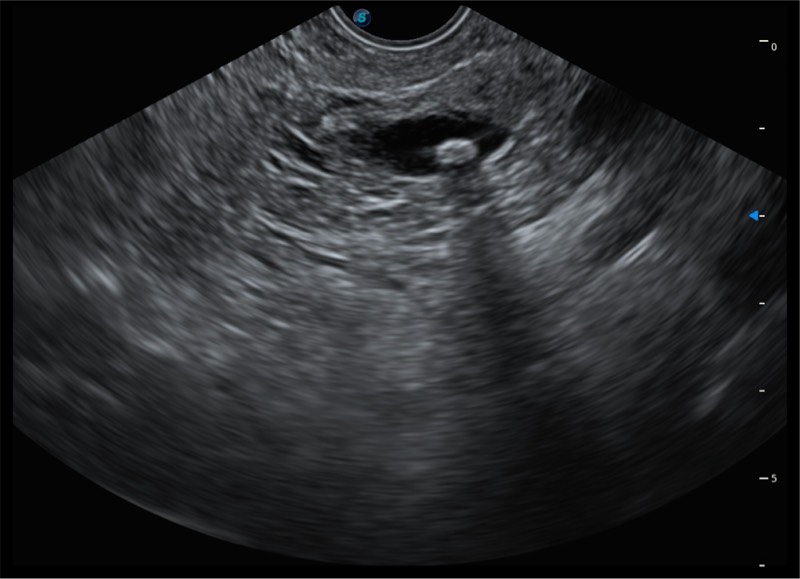

基于二十年的超声技术积累,玖鼎集团提供了最新一代的独立超声主机,在提供高质量图像的同时满足多学科使用。具备常见多普勒技术并提供弹性成像、声学造影等高端影像技术。新一代传感器具有更强的抗干扰能力并减少图像伪影。

150°超声扫描角度

4-12MHZ宽频输出